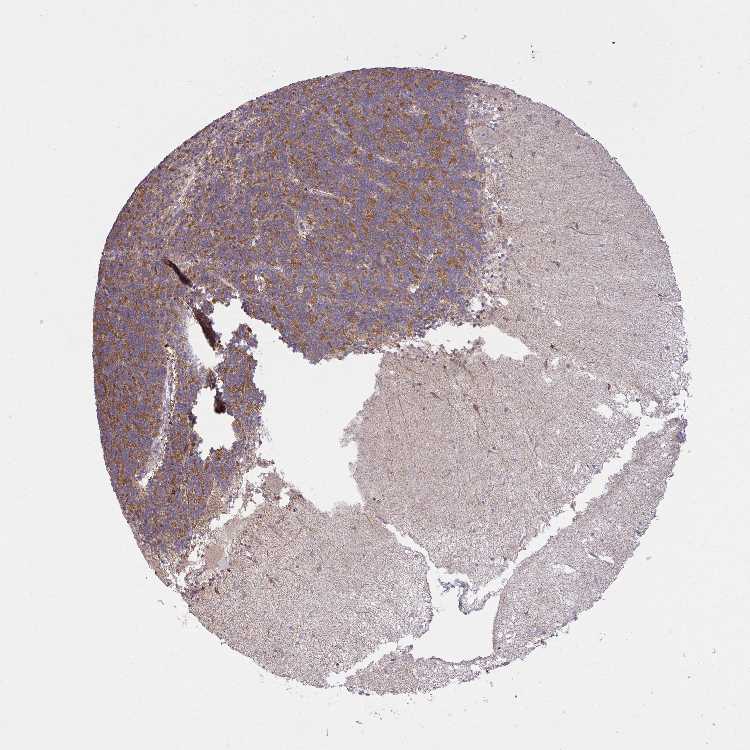

CEREBELLUM - Antibody stainingi

Antibody staining in the annotated cell types in the current human tissue is reported as not detected, low, medium, or high, based on conventional immunohistochemistry profiling in selected tissues. This score is based on the combination of the staining intensity and fraction of stained cells.

Each image is clickable and will lead to virtual microscopy that enables deeper exploration of all samples and also displays staining intensity scores, fraction scores and subcellular localization as well as patient and tissue information for each sample.

Antibody HPA057666Antibody HPA059092

Purkinje cells Not detectedNot detected

Cells in granular layer HighMedium